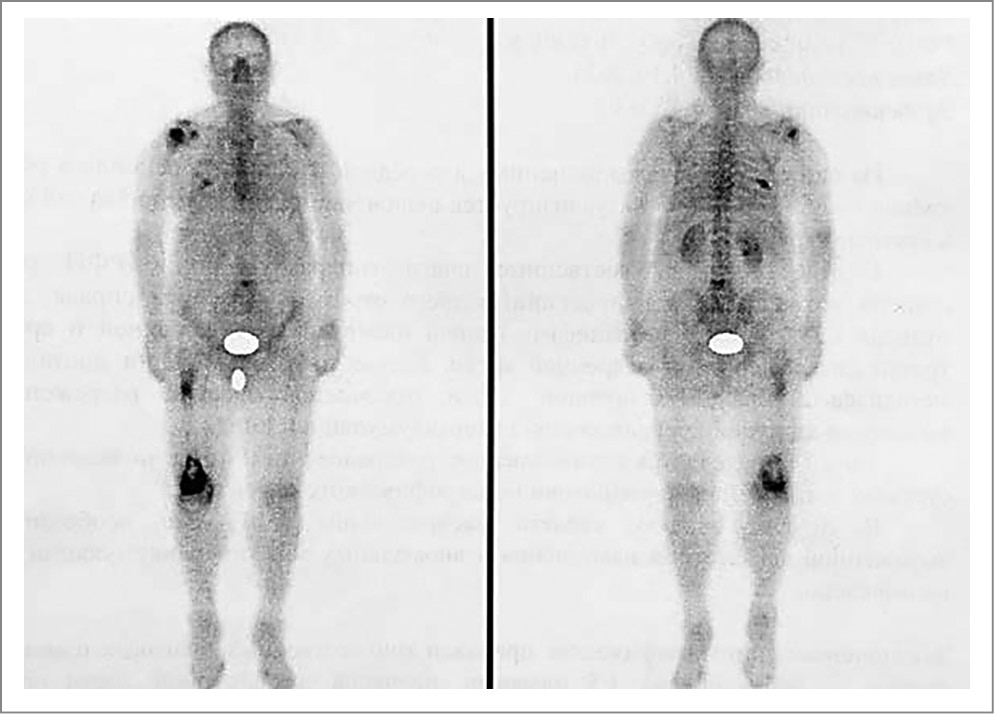

Для уточнения генеза костно-деструктивных изменений выполнена остеосцинтиграфия, выявлены очаги патологического накопления радиофармпрепарата в диафизе правой бедренной кости, эпифизе правой плечевой кости, VII ребре справа и LV позвонке (рис. 4).

Рис. 4. Остеосцинтиграфия. Очаги патологического накопления радиофармпрепарата в диафизе правой бедренной кости, эпифизе правой плечевой кости, VII ребре справа и LV позвонке.